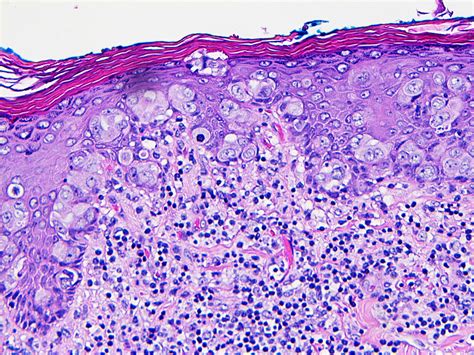

Paget's disease of the breast is a rare form of cancer that originates in the ducts beneath the nipple and areola. It is characterized by the presence of abnormal cells, known as Paget cells, which spread to the skin of the nipple and areola. These cells can cause changes in the appearance and texture of the nipple, making it essential to recognize the signs early.

• Biopsy: A biopsy involves taking a small sample of tissue from the affected area for laboratory analysis. This is the definitive way to confirm the presence of Paget cells and diagnose Paget's disease.

Understanding Paget's Nipple Pictures

Visual aids, such as Paget's nipple pictures, play a crucial role in educating both healthcare providers and patients about the condition. These images can help in recognizing the early signs and symptoms of Paget's disease, facilitating timely diagnosis and treatment. Here are some key points to consider when examining Paget's nipple pictures:

• Appearance: Look for changes in the color, texture, and shape of the nipple and areola. Common signs include redness, scaling, and crusting.